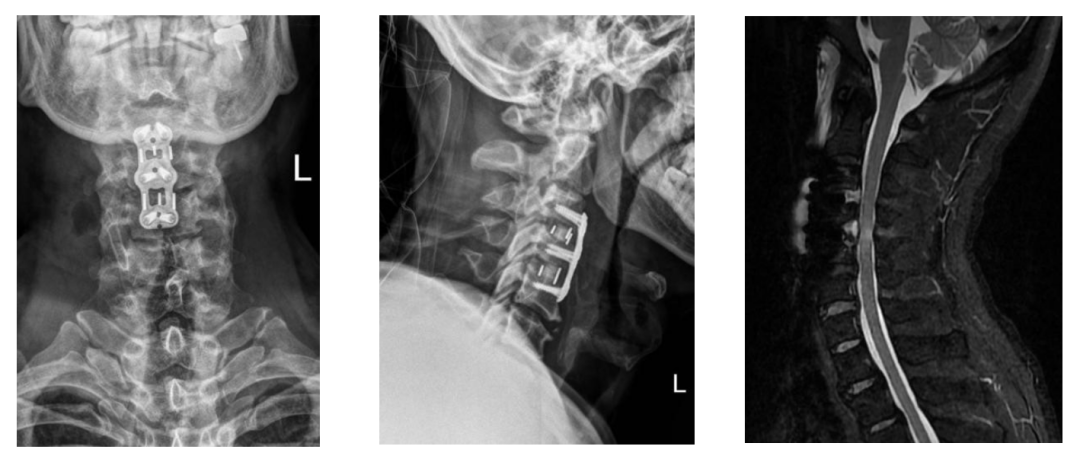

近日,我院中心院区脊柱外科张庆国主任团队,紧急救治了一位47岁头颈部外伤患者。看似普通的磕碰,竟让患者突发瘫痪,呼吸、大小便功能也受影响,送至我院后确诊为无骨折脱位型颈脊髓损伤。张庆国主任与刘淑恒主任、张高翔医师当天便开展急诊手术,仅1小时余就完成救治,术后患者神经功能快速恢复,与同类患者相比,神经恢复更加充分且快速,为这类凶险损伤的救治提供了范本。这种隐形创伤,极易被忽视,却暗藏终身残疾的风险!在此,脊柱外科张庆国主任提醒大家,看似轻微的头颈部外伤,绝不能掉以轻心。

无骨折脱位型颈脊髓损伤的核心特征的是:颈椎影像学检查未显示骨折或脱位,但脊髓已发生实质性损伤,这种“表里不一”的表现正是其凶险性的关键所在。

对于疑似此类损伤的患者,就医后需尽快完善颈椎磁共振(MR)等相关检查,以明确脊髓损伤情况及压迫来源。医生会根据患者的具体病情,制定个性化的诊疗方案。若符合手术指征,需及时开展手术治疗,手术的核心目标是精准解除脊髓压迫,尽可能保留和恢复神经功能,且在技术允许的前提下,会力求减少手术创伤、降低手术风险。